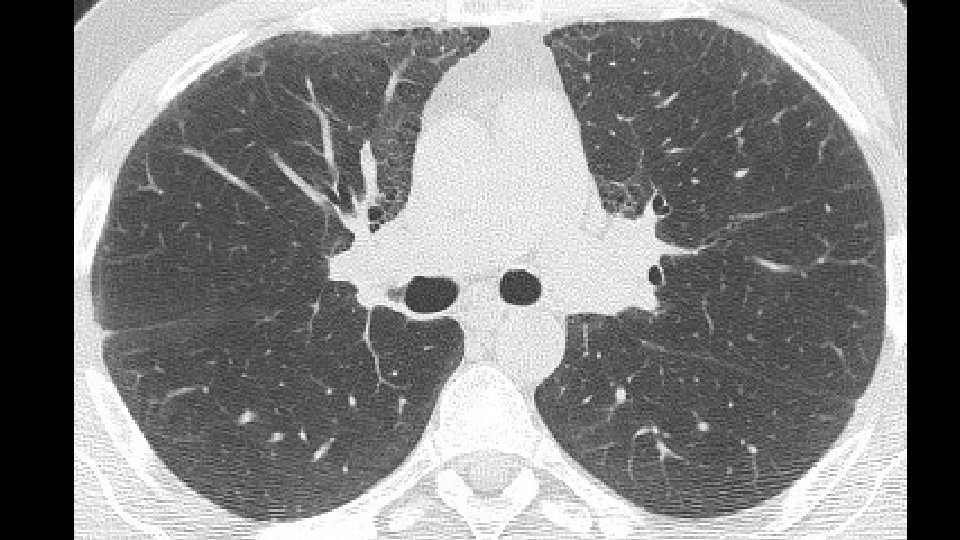

ADDITIONAL HISTORY Patient underwent five cycles of cyclophosphamide (750 mg/mq) EKG and LAB tests: Normal/negative Dyspnea persisted CT scan was repeated seven months later followed by a VATS B

Increase of coarseness

Increase of cysts in the contest of reticulation a ground glass attenuation